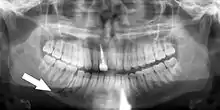

Plain film radiography

Traditionally, plain films of the mandible would be exposed but had lower sensitivity and specificity owing to overlap of structures. Views included AP (for parasymphsis), lateral oblique (body, ramus, angle, coronoid process) and Towne's (condyle) views. Condylar fractures can be especially difficult to identify, depending on the direction of condylar displacement or dislocation so multiple views of it are usually examined with two views at perpendicular angles.[11]

Panoramic radiograph of a simple mandible fracture of the right mandibular body, minimally displaced. Note that the teeth to the left of the fracture do not touch